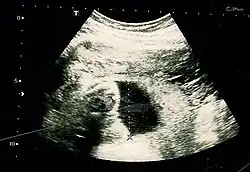

The result of an ultrasonography: a black and white image that shows a clear view of the interior abdomen

Obstetric ultrasonography is routinely used for dating the gestational age of a pregnancy from the size of the fetus, determine the number of fetuses and placentae, evaluate for an ectopic pregnancy and first trimester bleeding, the most accurate dating being in first trimester before the growth of the foetus has been significantly influenced by other factors.[22] Ultrasound is also used for detecting congenital anomalies (or other foetal anomalies) and determining the biophysical profiles (BPP), which are generally easier to detect in the second trimester when the foetal structures are larger and more developed.[23]

X-rays and computerized tomography (CT) are not used, especially in the first trimester, due to the ionizing radiation, which has teratogenic effects on the foetus.[24] No effects of magnetic resonance imaging (MRI) on the foetus have been demonstrated,[25] but this technique is too expensive for routine observation. Instead, obstetric ultrasonography is the imaging method of choice in the first trimester and throughout the pregnancy, because it emits no radiation, is portable, and allows for realtime imaging.[26]

The safety of frequent ultrasound scanning has not been confirmed. Despite this, increasing numbers of women are choosing to have additional scans for no medical purpose, such as gender scans, 3D and 4D scans.[27] A normal gestation would reveal a gestational sac, yolk sac, and fetal pole.[28]

The gestational age can be assessed by evaluating the mean gestational sac diameter (MGD) before week 6, and the crown-rump length after week 6. Multiple gestation is evaluated by the number of placentae and amniotic sacs present.[29]